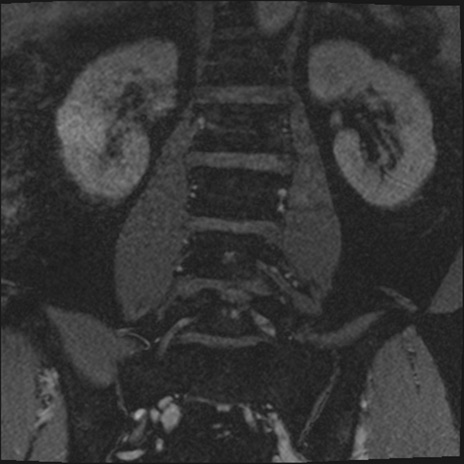

【整形】TIPS症例2 腰椎MRI 3D(冠状断像)

【症例】70歳代男性

【主訴】左下肢痛

【現病歴】2週間前くらいから腰痛、左下肢痛あり。左臀部から大腿、下腿外側のしびれが常時ある。歩行とともに同部位の痛みあり。

【身体所見】Lasegue70-/60+、Bragard-/±、PTR ±/±、ATR -/-、IP 5/5、TA 5/4、TS 5/5、EHL 右第1足趾なし/3、FHL 5/5、hypersthesia(-)、足背動脈触知良好

異常所見と診断は?